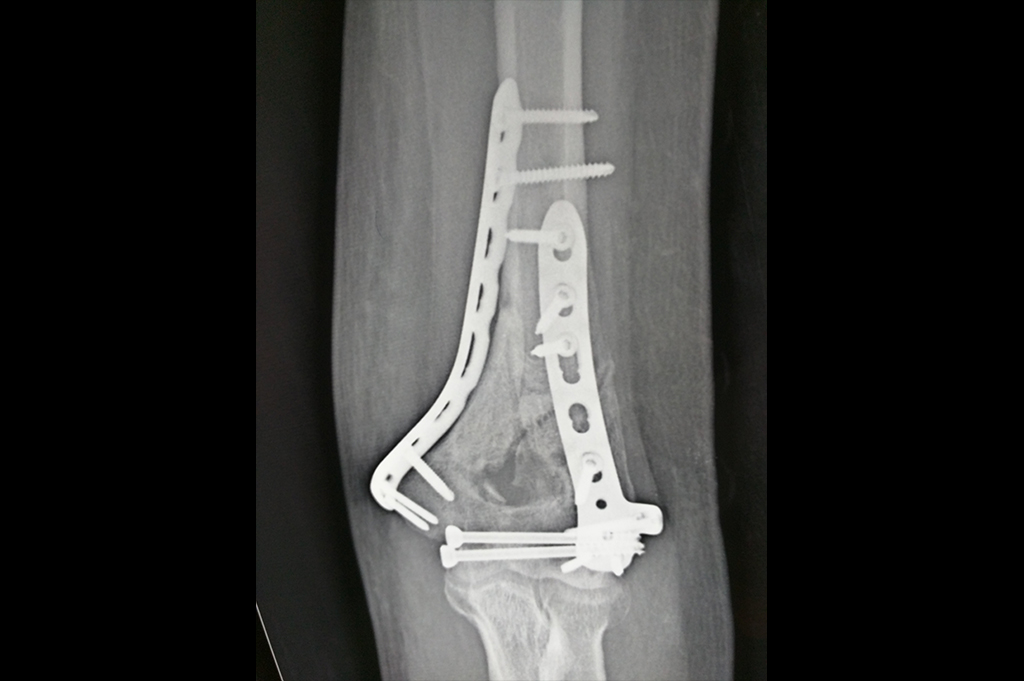

Distal Femur